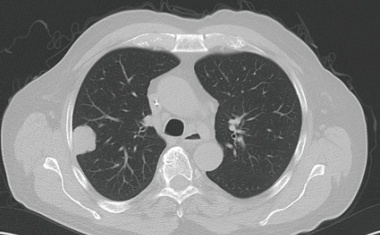

Viele Besonderheiten charakterisieren die Metastasierung des kolorektalen Karzinoms und des Mammakarzinoms insbesondere bei Befall von Leber und auch Lunge.